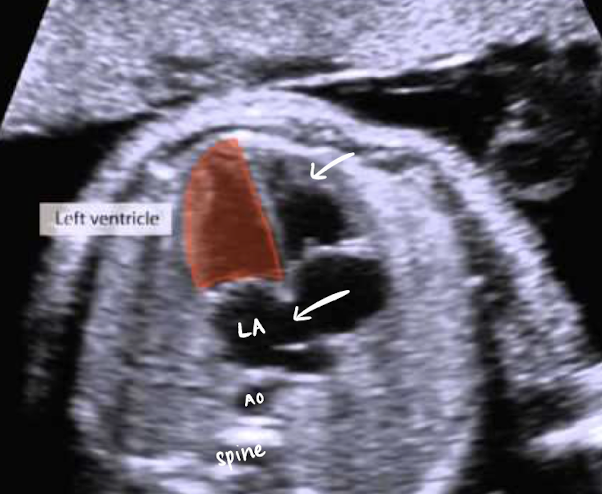

LA (left atrium)

receives blood from pulmonary veins (some) and foramen ovale (most)

sends oxygenated blood to LV via bicuspid/mitral valve (b/w LA and LV)

LA receives what type of blood and from where?

oxygenated blood; from foramen ovale and pulmonary veins

LV (left ventricle)

receives oxygenated blood from LA

sends oxygenated blood to the body via AO ← LVOT

LA is closest to AO and spine